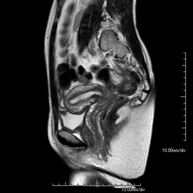

Prova diagnòstica no invasiva que consisteix en l'obtenció d'imatges d'alta definició anatòmica de l'abdomen mitjançant l'ús d'un camp electromagnètic i ones de ràdio (amb un emissor i un receptor). No utilitza radiació ionitzant. En aquesta exploració s'inclouen el fetge, el pàncrees, la melsa, la via biliar, la vesícula biliar, les glàndules suprarenals, els ronyons, l'aorta abdominal, la vena cava inferior, l'estómac, el duodè, etc. En alguns casos caldrà emprar contrast paramagnètic (Gadolini) per caracteritzar les lesions. - RM Pelvis femenina

Prova diagnòstica no invasiva que consisteix en l'obtenció d'imatges d'alta definició anatòmica de la pelvis mitjançant l'ús d'un camp electromagnètic i ones de ràdio (amb un emissor i un receptor). No utilitza radiació ionitzant. Es realitza per a l'estudi de patologies d'úter, d'ovari, de trompes i de vagina, ja siguin d'origen tumoral, inflamatori o vascular. També permet valorar les estructures adjacents localitzades a la pelvis i la identificació de les seves alteracions. De vegades és necessari l'ús de contrast intravenós (Gadolini) per caracteritzar les lesions. - RM Pelvis masculina

Prova diagnòstica no invasiva que consisteix en l'obtenció d'imatges d'alta definició anatòmica de la pelvis masculina mitjançant l'ús d'un camp electromagnètic i ones de ràdio (amb un emissor i un receptor). No utilitza radiació ionitzant. No requereix preparació prèvia. En algunes ocasions necessita l'ús de contrast paramagnètic (Gadolini) per caracteritzar les lesions. Aquesta prova permet valorar òrgans com la bufeta urinària, la unió entre els urèters i la bufeta, la pròstata, les vesícules seminals, la uretra i els ossos de la pelvis, entre d'altres. - RM de Fetge

Prova diagnòstica no invasiva que consisteix per obtenir d'imatges d'alta definició anatòmica de l'intestí mitjançant l'ús d'un camp electromagnètic i ones de ràdio (amb un emissor i un receptor). No utilitza radiació ionitzant. Normalment requereix l'ús de contrast paramagnètic (Gadolini). Està indicada principalment en el diagnòstic, el seguiment i el control de la resposta al tractament dels pacients amb Malaltia de Crohn. - RM Rectal

Prova diagnòstica no invasiva que consisteix en l'obtenció d'imatges d'alta definició anatòmica del recte mitjançant l'ús d'un camp electromagnètic i ones de ràdio (amb un emissor i un receptor). No utilitza radiació ionitzant. Normalment no requereix l'ús de contrast paramagnètic (Gadolini). Està indicada principalment en el diagnòstic, l'estadiatge i el seguiment del Càncer de recte. - RM de Paret abdominal